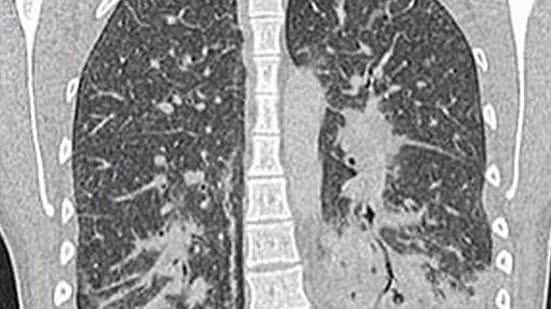

As imagens dos exames mostravam que a jovem tinha opacidades de vidro, geralmente ocorre junto com a consolidação nos pulmões. Consolidação se refere ao espessamento ou inchaço do tecido pulmonar, que acontece quando os espaços de ar nos pulmões se enchem de fluido, pus, sangue ou células.

Ela foi inicialmente diagnosticada com pneumonia bacteriana grave, que foi tratada com antibióticos por cinco dias, porém, devido a não melhora dos sintomas, os médicos realizam um exame de raio-x que indicou manchas translúcidas por todos os pulmões, sugerindo que eles estavam cheios de líquido e apresentavam sinais de danos nos tecidos.